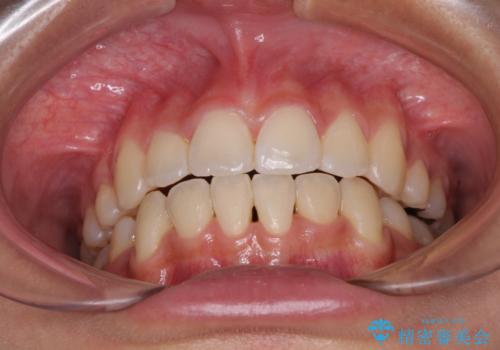

半年ほどで前歯のデコボコは改善され、汚れの溜まりやすさは解消されました。

抜歯スペースを閉じるために期間がかかりましたが、当初予定通り2年強で終えることができました。